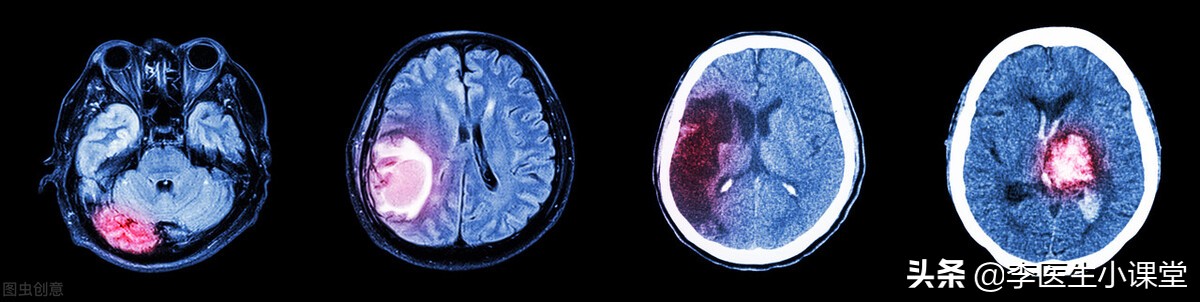

脑溢血也就是我们通常所说的脑出血(ICH), 是一种非外伤引起的脑实质内出血,血液从血管中溢出到脑策划中, 出血部位常出现在大脑半球、脑干以及小脑等处,在急性心脑血管疾病中脑出血患者占比较多,且致死率较高。

临床上根据大脑内血肿的发展过程,将其分为急性期、吸收期以及囊变期。